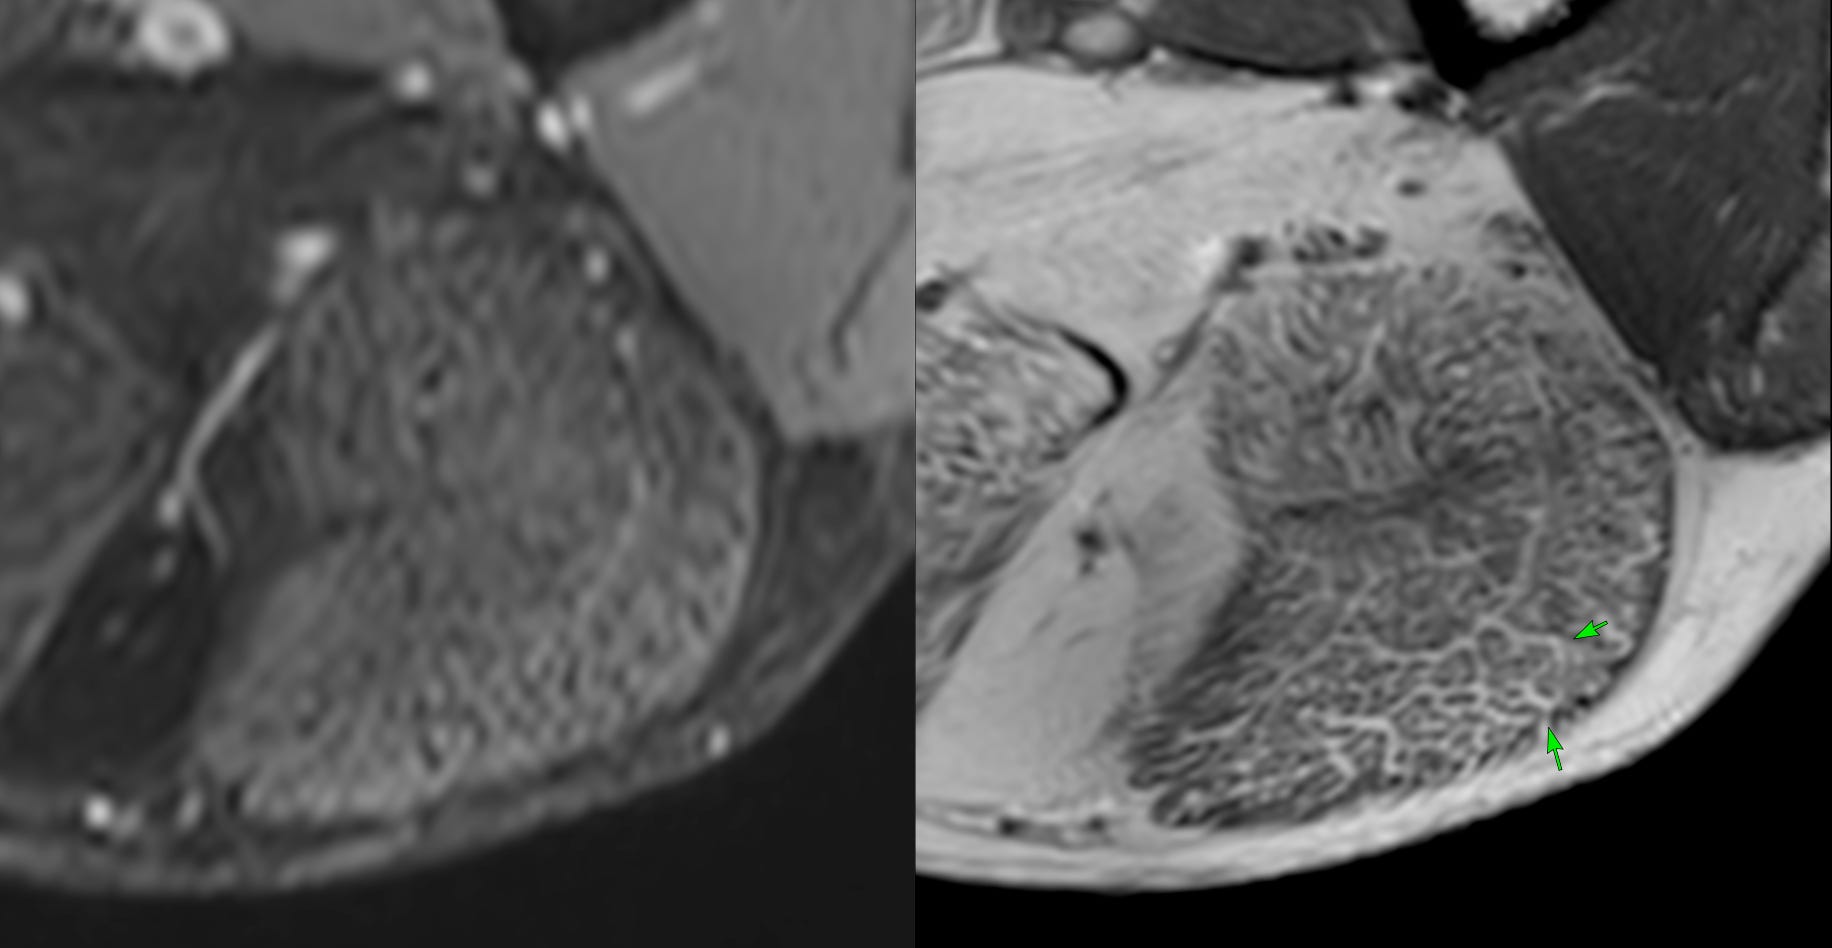

Case 63: The Honeycomb Pattern of Myositis

What is striking is the honeycomb pattern

The video describes the classic honeycomb pattern in this patient’s muscles and the implications and compares with the other patterns - fascial and peripheral/foggy described earlier in previous videos.